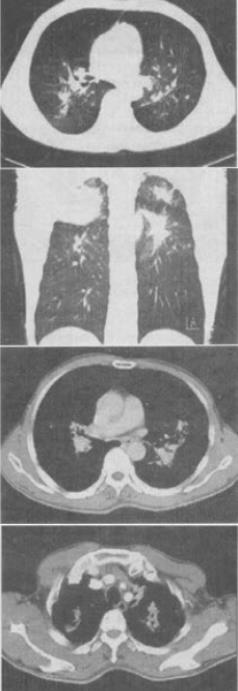

患者男,55岁,呼吸困难,气喘,查体桶状胸体症,CT如图,最可能的诊断是()。

A、双上肺结核

B、左上肺结核,右上肺癌

C、间质性肺炎

D、右上肺癌并肺内转移

E、矽肺

E